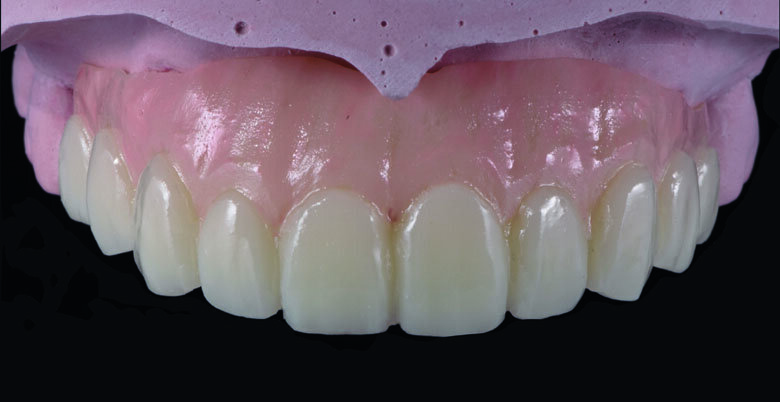

Fig 19. Completed Provisional Profile Prosthesis with gingival aesthetics that mimic nature

Provisional full arch bridge fabrication (Fig. 8 - 19)

Preparation cast with a diagnostic wax-up ca st was sent to a local laboratory for scanning and transforming into STL (Stereolithography) digital impression file. (Fig 8,9.) Two sets of STL impressions were super-imposed in the software in order to subtract the overlapping data. This process was done in order to transform the diagnostic wax-up into the STL digital impression. Consequently, the STL data was sent to the laboratory for milling. (Fig10.) A monochromatic milled-PMMA temporary bridge was fabricated in a local laboratory and returned to the dentist for composite layering. (Fig 11.) Gingival cutback was made to create sufficient gingival space for pink composite layering (Fig 12). Prior to composite layering CeraResin Bond 1 was applied and left for 10 seconds to prime the surface, followed by application of CeraResin Bond 2 for 10 seconds and light cured for 20 seconds (Fig 13.). Ceramage Indirect Composite gingival shade GUM-O (GUM Opaque) was applied to mask the color of PMMA (Fig 14.). GUM-D (GUM Dark) was applied on the attached gingiva area to the buccal flange (Fig 15.). GUM-L (GUM Light) was applied in the region of free gingiva (Fig 16.). F-GUM-R (Flowable GUM Red) and F-W (Flowable GUM White) were painted to mimic the mucogingival junction and vascular alveolar mucosa (Fig 17.) GUM-T (GUM Translucent) was applied to reproduce of reddish translucent gingiva areas (Fig 18) to achieve natural gingival aesthetics.

Contouring, Finishing and Polishing of temporary restoration

Meticulous finishing and polishing of the restoration is a crucial step to achieving the desired aesthetics. Dura-Green stone was used to contour the macro anatomical details while the Robot Carbide Fissure Bur was used to shape the interproximal and papilla areas. The course silicone points followed by Dura-Polishing paste Al2O3 with a medium strong brush was used to finish and pre-polish the restoration. Dura-Polish DIA, diamond polishing paste was applied with a fine brush followed by the cotton buff to achieve the final high-luster polishing (Fig 19.)1.